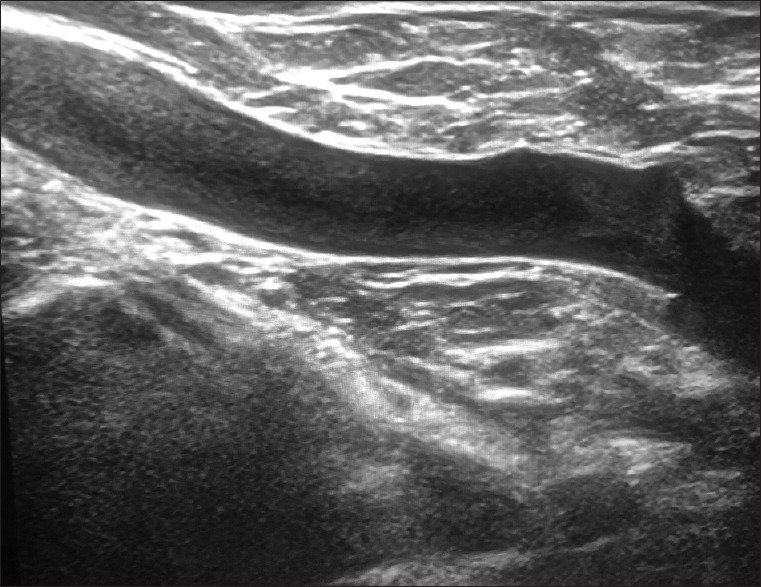

Methods: Five thousand four hundred and twenty cases were reviewed in our clinic for diagnostic breast imaging between May 2021 and May 2022. Five thousand three hundred and two of the cases were female, while 118 were male. Duplex Doppler scanning was used to assess the subclavian vein and the axillary venous structures. The same radiologist performed all examinations; in cases where suspicion was warranted, a second radiologist's opinion was acquired. The diagnosis was confirmed by consensus.

Results: In 52 cases, McCleery syndrome was identified. Between the ages of 36 and 54 years, the average age was 47 years. In four of the patients, magnetic resonance venography supported the diagnosis. In most cases, McCleery syndrome was unilateral. In only two cases was it bilateral. The incidence of McCleery syndrome was 0.95% in our study. Pain was the most often reported symptom (53.8% of 28 cases). No symptoms were reported in 26.9% of the patients.

Conclusion: During a breast ultrasound, radiologists should be aware of McCleery syndrome while assessing the axilla.